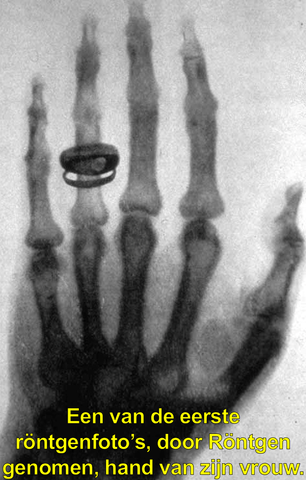

n werk herhaalde hij in eerste instantie experimenten van tijdgenoten met het zenden van kathodestraling door vacuümbuizen. In 1895, hij was toen 50 jaar, raakt hij geobsedeerd door het onderzoek naar kathodestralen. Daar geeft hij zijn volledige aandacht aan. Begin november is hij 's avonds bezig met proefnemingen. Het is donker. Röntgen ziet een fluorescerende plaat oplichten. Hij concludeert dat de buis een nieuw soort stralen produceert en reageert met fluorescerend materiaal. Hij noemt deze nieuwe stralen ‘X-stralen’, naar de onbekende factor X in wiskundige formules. In de meeste talen wordt röntgenstraling nog steeds zo genoemd. Röntgen experimenteert verder met de X-stralen en ontdekt dat ze niet door hard materiaal, zoals metaal en been, dringen. Dit demonstreert hij door een ‘röntgenfoto’ te maken van de hand van zijn vrouw. Haar botten en trouwring, die de straal niet doorlieten, werden zichtbaar op de fotoplaat. Het zachte materiaal, de huid en ander weefsel, liet de straling wel door. Op de ontwikkelde foto zijn tot grote schrik van zijn vrouw de botjes van haar hand en haar twee ringen duidelijk zichtbaar. Ze schijnt hierbij uitgeroepen te hebben "Ik zie mijn eigen dood."